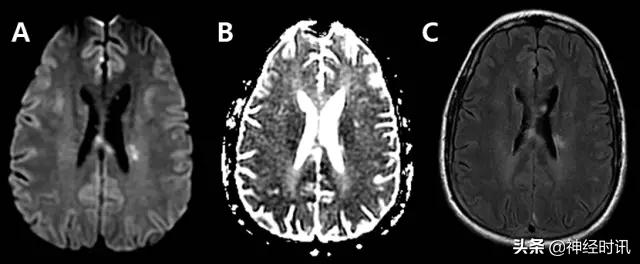

MELAS表现为恶心、呕吐、癫痫发作、肌无力和急性神经功能缺损,通常在40岁以前发病。MRI显示皮质和皮层下白质T2高信号、水肿和弥散受限。鉴别因素包括疾病进展不同阶段的多发病灶,急性病灶内同时存在弥散受限和增加,非血管性分布,以及好发于后部顶叶和枕叶(图6)。

图6 一例48岁男性,近期2次左侧PCA分布区梗死,伴神经功能缺损加重,新发认知功能障碍和意识障碍。最终诊断为MELAS,FLAIR显示左侧后顶颞针叶非血管性分布的皮层水肿(A:FLAIR),同时伴弥散受限和弥散增加(B:DWI;C:ADC)。